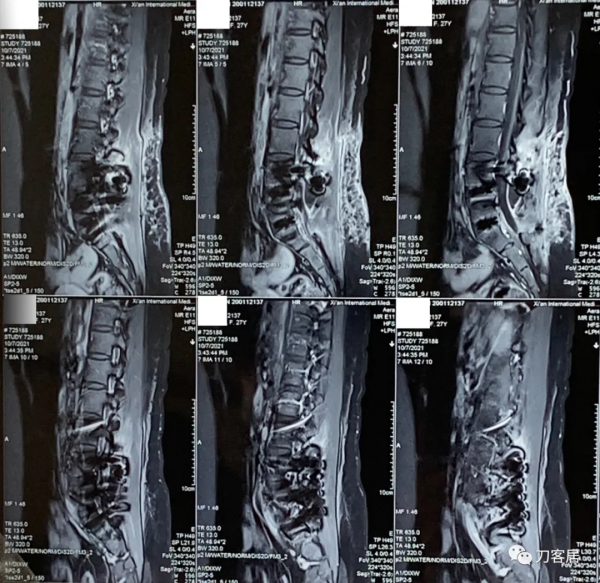

圖20. 20211007術後44天,腰椎MRI提示腰椎切口內液性聚集,但切口周圍軟組織內混雜訊號好轉。

圖21. 20211007術後44天,腰椎MRI提示腰椎切口內液性聚集,但切口周圍軟組織內混雜訊號好轉。

圖22. 20211007術後44天,腰椎MRI提示腰椎切口內液性聚集,但切口周圍軟組織內混雜訊號好轉,但該T1相提示術野後部軟組織內仍有異常訊號影。

圖23. 20211007術後44天,腰椎MRI提示腰椎切口內液性聚集,但切口周圍軟組織內混雜訊號好轉,但該T1相提示術野後部軟組織內仍有異常訊號影。

圖24. 20211007術後44天,腰椎MRI提示腰椎切口內液性聚集,但切口周圍軟組織內混雜訊號好轉,但該T1相提示術野後部軟組織內仍有異常訊號影。

圖25. 20211007術後44天,腰椎MRI橫截面掃描提示腰椎切口內液性聚集,但切口周圍軟組織內混雜訊號好轉,但術野後部軟組織內仍有異常訊號影。

圖26. 20211007術後44天,腰椎MRI橫截面掃描提示腰椎切口內液性聚集,但切口周圍軟組織內混雜訊號好轉,但術野後部軟組織內仍有異常訊號影。

圖27. 20211007術後44天,腰椎MRI橫截面掃描提示腰椎切口內液性聚集,但切口周圍軟組織內混雜訊號好轉,但術野後部軟組織內仍有異常訊號影。